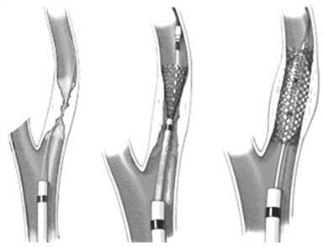

经皮经腔血管成形术(percutaneous transluminal angioplasty,PTA)是经导管等器械扩张、再通动脉粥样硬化或其他原因所致的血管狭窄或闭塞性病变的方法,近年来也用于胸、腹主动脉瘤及假性动脉瘤的腔内隔绝治疗,主要方法有球囊血管成形术(balloon angioplasty)和血管内支架置入术(endovascular stent)等。治疗原理:对狭窄段血管组织有限度地损伤和撕裂,扩大其管径,受损组织再修复达到管腔重建;支架则是利用其支撑力将狭窄的血管撑开;覆膜支架将扩大的血管腔或有异常通道的瘘口分隔开,形成人工通道。

1.球囊血管成形术 最佳适应证为大、中血管的局限短段狭窄或闭塞。大多数动、静脉系统的狭窄或闭塞甚至人造血管、移植血管的狭窄或闭塞均可选择球囊血管成形术进行治疗(图21-18至图21-20)。

图21-18 球囊血管成形术示意